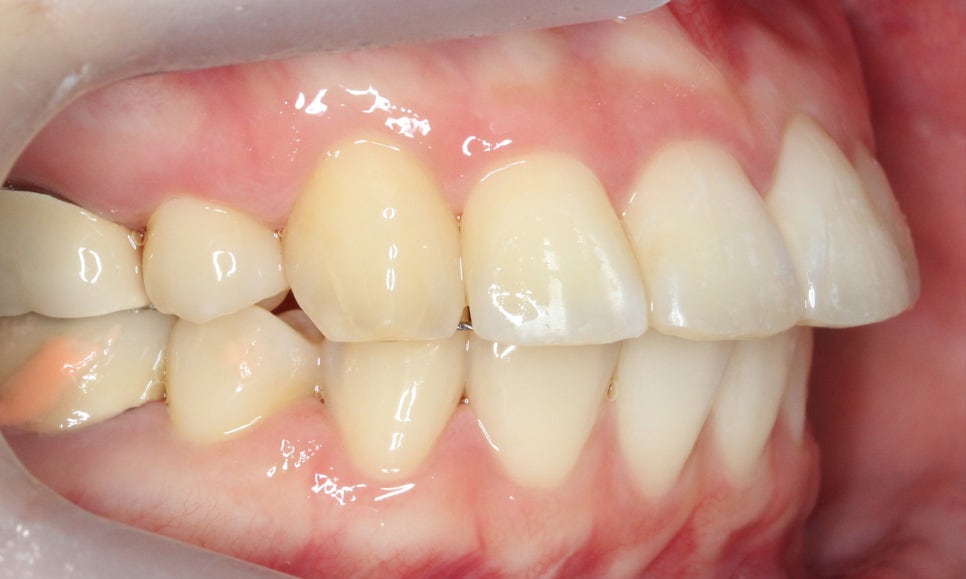

좌우 교합 평면의 모습을 보면

협측 사진에서 중절치의 돌출감이

심한 모습을 볼 수 있는데요,

구치부의 교합 상태를 보니

윗니가 과도하게 앞으로

튀어나와 있는 2급 부정교합이

의심되는 모습입니다.

이러한 경우 전치부 교정만으로는

상하악 교합을 바르게 교정하기 어려운데요,

따라서 전체교정으로 치열을 가지런하게

바꾸고 상하악 교합도 정상적으로 맞출 수 있습니다.